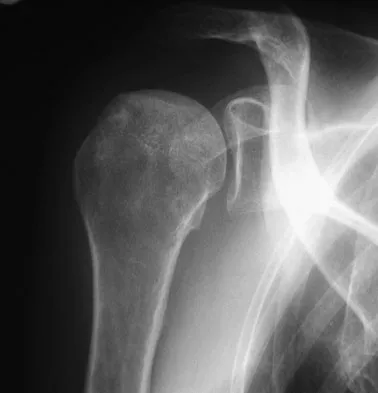

Figure 35 shows the radiograph of a 12-year-old boy who fell off a snowmobile and landed on his left shoulder. He has a closed injury. Management should consist of

Explanation

Proximal humeral fractures in children are classified as metaphyseal or Salter-Harris type I or II fractures, and most of these fractures are treated with closed methods. Eighty percent of the growth of the humerus comes from the proximal physis; therefore, tremendous remodeling potential is present. Indications for open reduction include open fractures or severely displaced fractures in adolescents with minimal growth remaining. Acceptable limits of reduction in adolescent proximal humeral fractures include bayonet apposition and angulation of less than 35 degrees. Common blocks to reduction in adolescents include the biceps tendon and periosteum. For this fracture, use of a shoulder sling without reduction will lead to healing and an excellent result as the proximal humerus remodels. Kohler R, Trillaud JM: Fracture and fracture separation of the proximal humerus in children: Report of 136 cases. J Pediatr Orthop 1983;3:326-332. Beaty JH: Fractures of the proximal humerus and shaft in children. Instr Course Lect 1992;41:369-372. Dobbs MB, Luhmann SL, Gordon JE, et al: Severely displaced proximal humeral epiphyseal fractures. J Pediatr Orthop 2003;23:208-215. Beringer DC, Weiner DS, Noble JS, et al: Severely displaced proximal humeral epiphyseal fractures: A follow-up study. J Pediatr Orthop 1998;18:31-37.